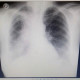

Alodokter, selamat malam dok, ijin share kasus, perempuan usia 68 thn datang dengan keluhan batuk sudah 4 minggu dan sulit bernafas saat berbicara banyak. Batuk dikatakan kadang berdahak kadang kering. Sudah mendapat terapi dari dokter Sp.P dengan diagnosis Pneumonia namun membaik hanya sedikit. SaO2 95% udara ruangan, BP 150/100 mmhg. Pemeriksaan fisis tidak ada ronki atau wheezing. Chest X-Ray dengan hasil terlampir. WBC 48.000.

Yang ingin saya tanyakan apakah klinis pasien dan radiologi sesuai dengan Pneumonia atau mungkinkah ini merupakan massa/tumor di paru kanan? Apakah pada pneumonia WBC bisa naik sebanyak itu dok?

Klo dilihat dari konsolidasinya mengarah ke pnemonia dok, klo massa kurang padat gambaran konsolidasinya, jg ada seperti cavitas diameter kecil diparu kanan,disarankan cek dahak dok untuk menyingkirkan diagnosa tb paru

Jika berdasarkan klinis dan ronsen paru maka kemungkinan suatu Tumpar D disertai sekunder infeksi (Misalnya suatu Pneumonia) dengan DD sbb :

- Pneumonia

- Partial atelektasis.

Sebaiknya dilakukan pemeriksaan CT Scan Thx kontras dan jika didapatkan kesan suatu tumor paru maka bisa dilakukan Fiberoptic bronchoscopy untuk pengambilan sampel biopsi PA